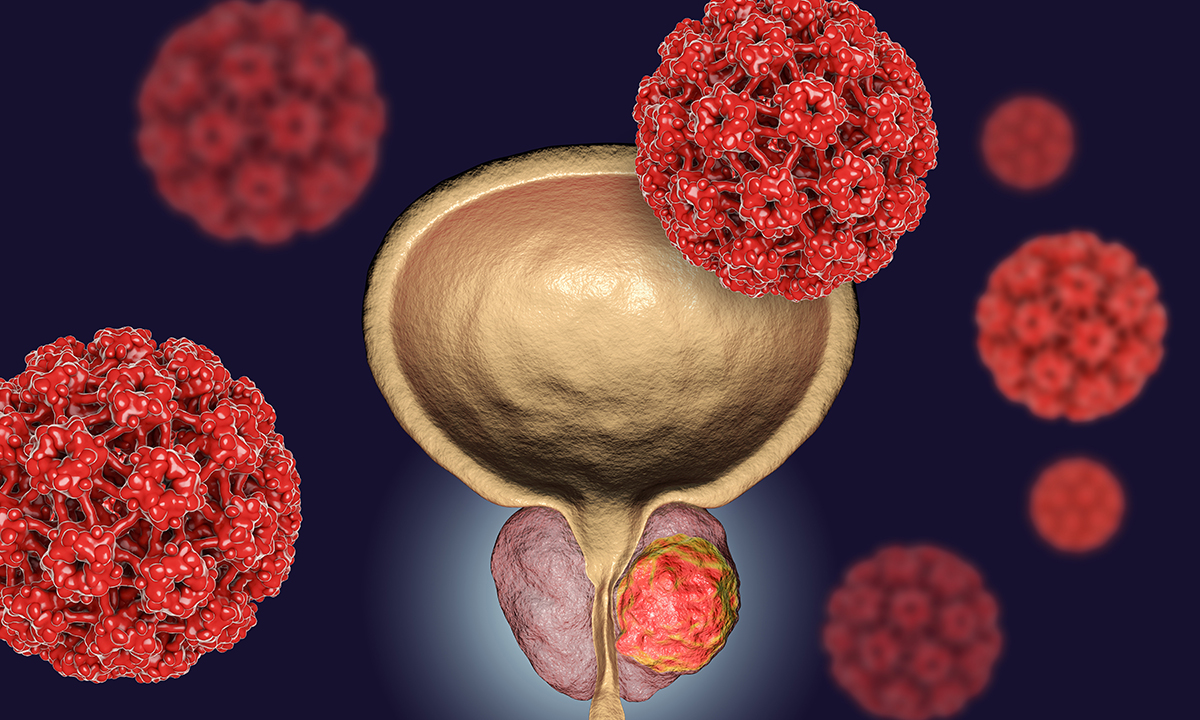

Un nuevo estudio para detectar cáncer de próstata, es muy precisa

Un nuevo estudio para detectar cáncer de próstata supera al análisis de sangre.

Hasta ahora el análisis de sangre era el método más efectivo para detectar esté tipo de cáncer. Básicamente lo que se hacía es que se analizaban los niveles del antígeno prostático específico (PSA), el cual justamente evita el crecimiento de células cancerígenas en está zona. Ahora el Instituto de Investigación del Cáncer de Londres (ICR) creó un nuevo método el cual solo requiere una muestra de saliva.

La nueva prueba lo que hace es analizar más de 130 variaciones del ADN lo que brinda un margen muchísimo más grande. Esté método lleva 10 años siendo probado y en estudios clínicos y por fin cumplió todos los requisitos para salir de la fase de pruebas. Aquí se demostró que era mejor que el estudio sanguíneo por dos simples elementos que se complementan. Estudia muchas más variables por lo que puede encontrar más cosas y al analizar tanta información se generan menos “falsos positivos“.

Los investigadores terminan diciendo que otra ventaja que tiene el nuevo estudio es que es mucho más “agradable” para el paciente y mucho más económico. Ahora la persona ya no deberá ir a un laboratorio clínico a que le saquen sangre, ahora en su casa simplemente deberá frotar un “recolector” especial y eso lo lleva a que lo analicen. Esto es especialmente útil si la persona tiene fobia a las agujas, especialmente porque este miedo es uno de los más comunes en el mundo y puede ser tan grave que paralicé a la persona o le generé un ataque de pánico.